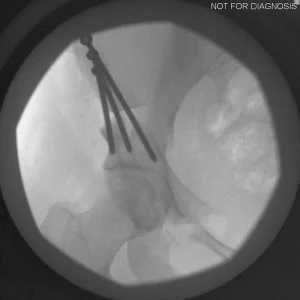

During a PAO, the surgeon carefully cuts the bone around the hip socket and repositions it to provide better coverage of the femoral head. The socket is then fixed in its new position using screws. The goal is to improve hip stability, reduce pain, and preserve the patient’s natural hip joint.

• Screws shown securing the acetabulum in its new position

• The socket is repositioned and fixed with screws